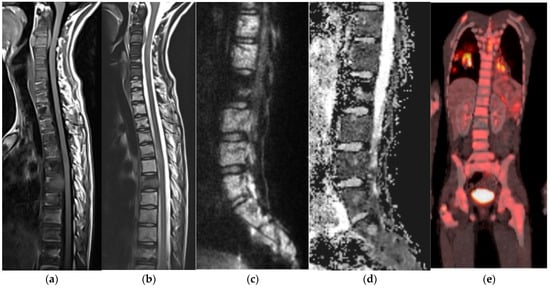

Ewing Sarcoma

Langerhans Cell Histiocytosis